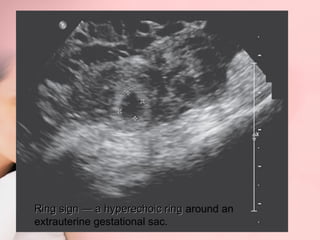

HHyyppeerreecchhooiicc rriinngg aarroouunndd

ggeessttaattiioonnaall ssaacc iinn aaddnneexxaall rreeggiioonn

Ring sign —— a hyperechoic ring around an

extrauterine gestational sac.